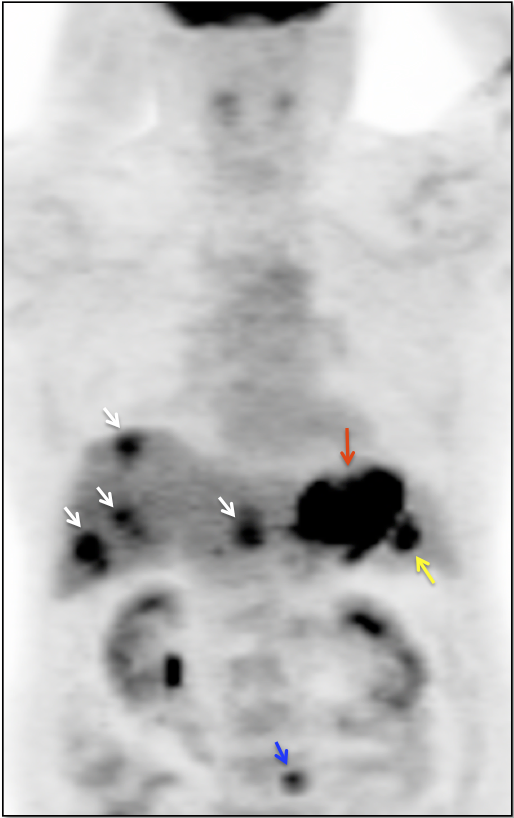

4. Abdomen & Pelvis

- FDG-Avid Adrenal Gland Algorithm

- Therapy-Induced Splenic Activation

- Peritoneal Carcinomatosis

- Distant Disease: Most commonly to the liver, peritoneum, lung and bone.

Criteria for “Active Malignancy”:

The difficulty with PET/CT imaging and gastric cancer is that it is both easy to overlook and easy to over-call.